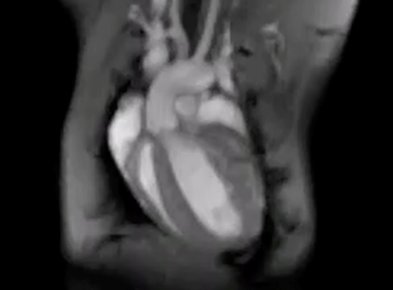

Cardiac regeneration becomes possible

In mice reprogramming of energy metabolism restores cardiac function after infarction more